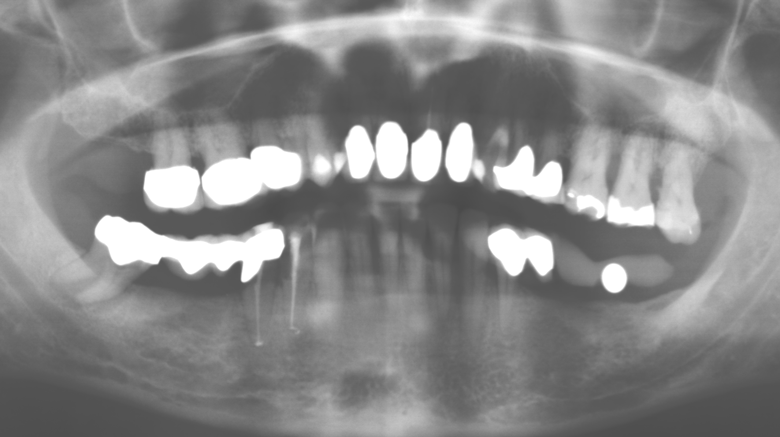

Fig. 3: Panoramic radiograph after ten years with implants.

The ten-year check-up revealed no indications of advancing clinical attachment loss or peri-implant bone substance loss (Fig. 3).